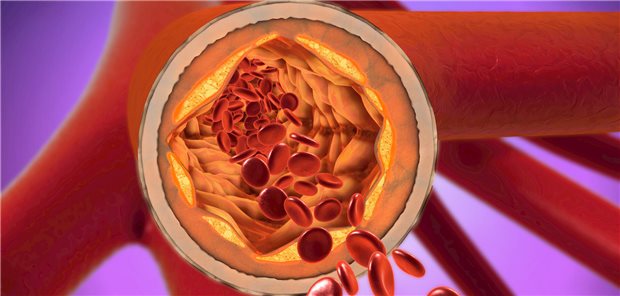

Lipidsenkung

LDL-Cholesterin: PCSK9-Inhibitor Evolocumab reduziert Risiko für erstes kardiovaskuläres Ereignis